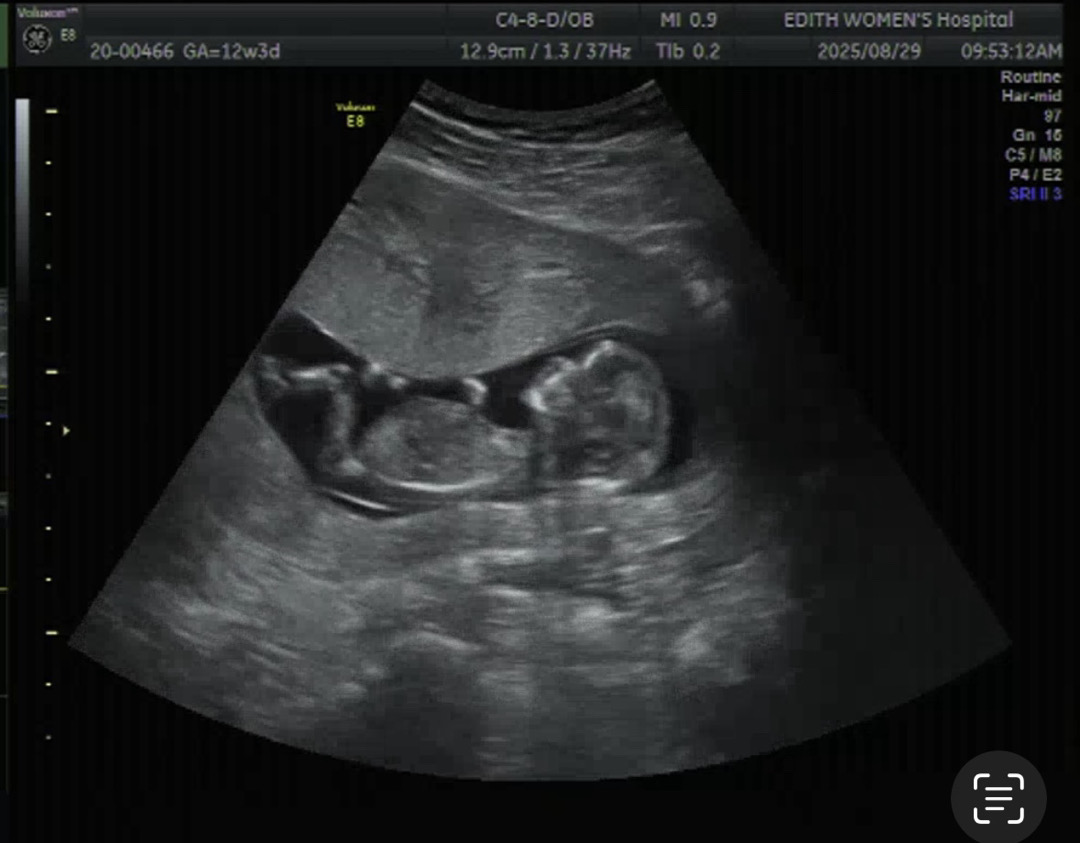

12주 각도법 봐주시면 감사하겠습니다!

베이비빌리AI로 하니.. 아들도 나오고 딸도 나오니😂 뭐가 맞는지 모르겠네용🤣🤣 한 번만 봐주시면 감사하겠습니다~